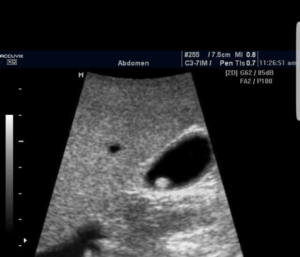

Doenças da Vesícula BiliarOs pólipos são lesões que crescem na parede interna da vesícula. A maioria é benigna, porém alguns apresentam risco de transformação maligna. Critérios que sugerem maior risco incluem:

• Tamanho maior que 10 mm

• Crescimento progressivo

• Lesão única

• Idade acima de 50 anos

• Associação com cálculos

• Presença de sintomas

Pólipos pequenos e estáveis podem ser acompanhados com ultrassonografia periódica.